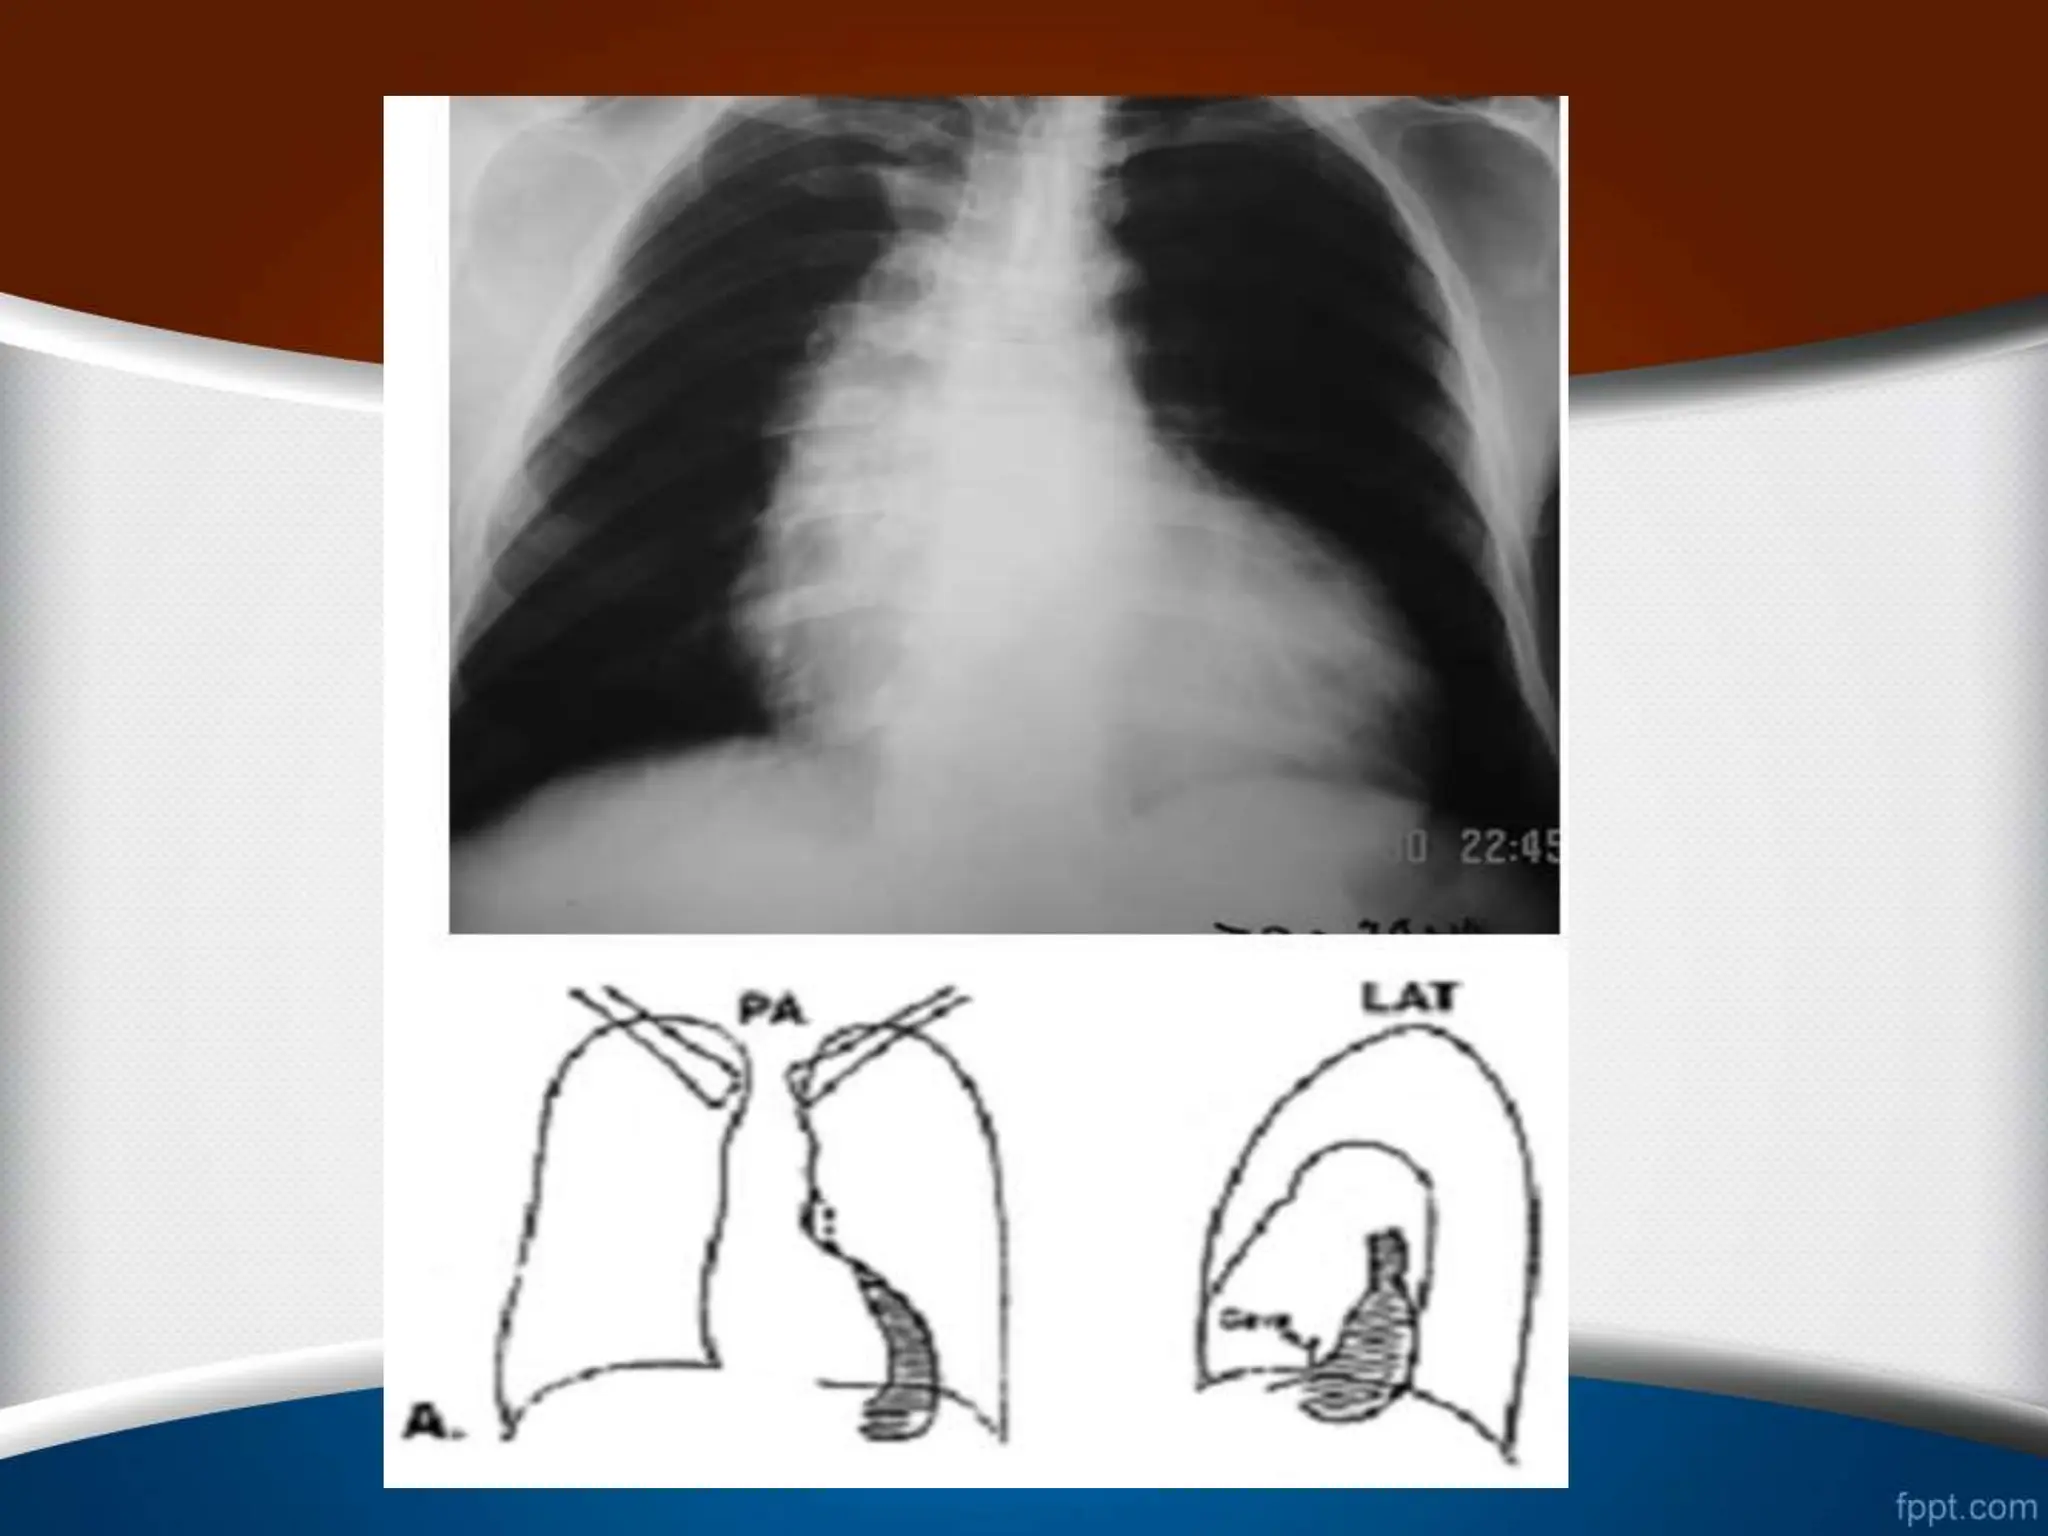

• 3 . ‫آلوئوالر‬ ‫ادم‬ • ‫بی‬ ‫مایع‬‫نشت‬ ،‫گویند‬ ‫می‬ ‫آلوئوالر‬ ‫ادم‬ ‫که‬ ‫سوم‬ ‫مرحله‬ ‫در‬ ‫ن‬ ‫ش‬ ‫تخلیه‬ ‫لنفاوی‬ ‫درناژ‬ ‫افزایش‬ ‫با‬ ‫تواند‬ ‫نمی‬ ‫بافتی‬ ‫ود‬ . ‫مایع‬ ‫لذا‬ ‫و‬ ‫کند‬ ‫می‬ ‫ایجاد‬ ‫آلوئوالر‬ ‫ادم‬ ‫و‬ ‫کند‬ ‫می‬ ‫نشت‬ ‫ها‬ ‫آلوئول‬ ‫در‬ ‫آمدن‬ ‫وجود‬ ‫به‬ ‫باعث‬ ‫پلور‬ ‫فضای‬ ‫به‬ ‫آن‬ ‫نشت‬ ‫طرفی‬ ‫از‬ ‫شود‬ ‫می‬ ‫پلور‬ ‫افیوژن‬

• 87.